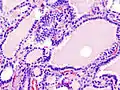

Hyperthyroidism is one of the most common endocrine conditions affecting older domesticated housecats. In the United States, up to 10% of cats over ten years old have hyperthyroidism.[54] The disease has become significantly more common since the first reports of feline hyperthyroidism in the 1970s. The most common cause of hyperthyroidism in cats is the presence of benign tumors called adenomas. 98% of cases are caused by the presence of an adenoma,[55] but the reason these cats develop such tumors continues to be studied.

The most common presenting symptoms are: rapid weight loss, tachycardia (rapid heart rate), vomiting, diarrhea, increased consumption of fluids (polydipsia), increased appetite (polyphagia), and increased urine production (polyuria). Other symptoms include hyperactivity, possible aggression, an unkempt appearance, and large, thick claws. Heart murmurs and a gallop rhythm can develop due to secondary hypertrophic cardiomyopathy. About 70% of afflicted cats also have enlarged thyroid glands (goiter). 10% of cats exhibit "apathetic hyperthyroidism", which is characterized by anorexia and lethargy.[56]